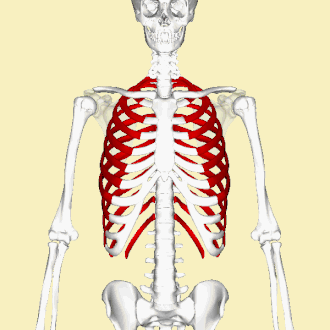

Rib cage

The first seven sets of ribs, known as "true ribs", are attached to the sternum by the costal cartilages. The first rib is unique and easier to distinguish than other ribs. It is a short, flat, C-shaped bone, and attaches to the manubrium.[6] The vertebral attachment can be found just below the neck at the first thoracic vertebra, and the majority of this bone can be found above the level of the clavicle. Ribs 2 through 7 then become longer and less curved as they progress downwards.[7] The following five sets are known as "false ribs", three of these sharing a common cartilaginous connection to the sternum, while the last two (eleventh and twelfth ribs) are termed floating ribs.[2] They are attached to the vertebrae only, and not to the sternum or cartilage coming off of the sternum.

In general, human ribs increase in length from ribs 1 through 7 and decrease in length again through rib 12. Along with this change in size, the ribs become progressively oblique (slanted) from ribs 1 through 9, then less slanted through rib 12.[7]

The rib cage is separated from the lower abdomen by the thoracic diaphragm which controls breathing. When the diaphragm contracts, the thoracic cavity is expanded, reducing intra-thoracic pressure and drawing air into the lungs. This happens through one of two actions (or a mix of the two): when the lower ribs the diaphragm connects to are stabilized by muscles and the central tendon is mobile, when the muscle contracts the central tendon is drawn down, compressing the cavity underneath and expanding the thoracic cavity downward. When the central tendon is stabilized and the lower ribs are mobile, a contraction of the diaphragm elevates the ribs, which works in conjunction with other muscles to expand the thoracic indent upward.